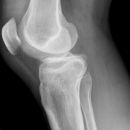

Kniegelenk